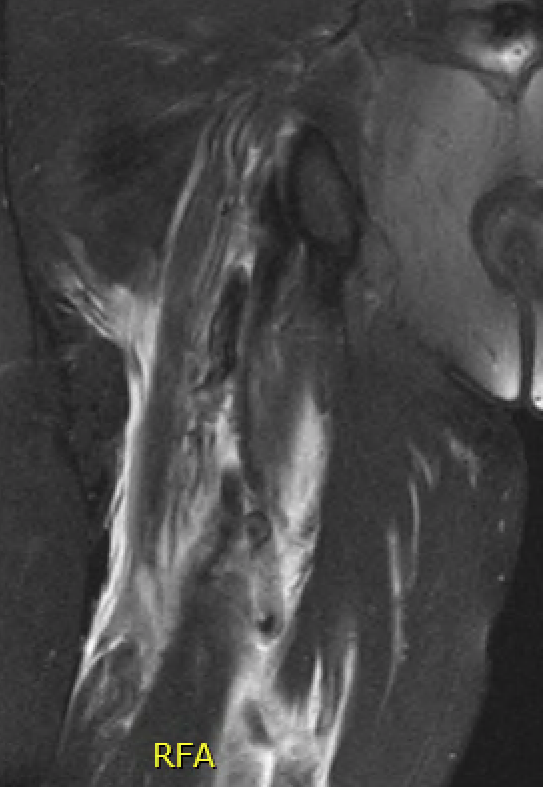

Proximal hamstring tear on right (red circle), normal insertion on tuberosity on left (blue circle)

Proximal hamstring avulsion on right - red circle is retracted hamstring tendon, blue circle is normal insertion on left

Proximal hamstring tear on right (red circle), normal insertion on left (blue circle)

Proximal hamstring avulsion, with tendon floating in hematoma / seroma